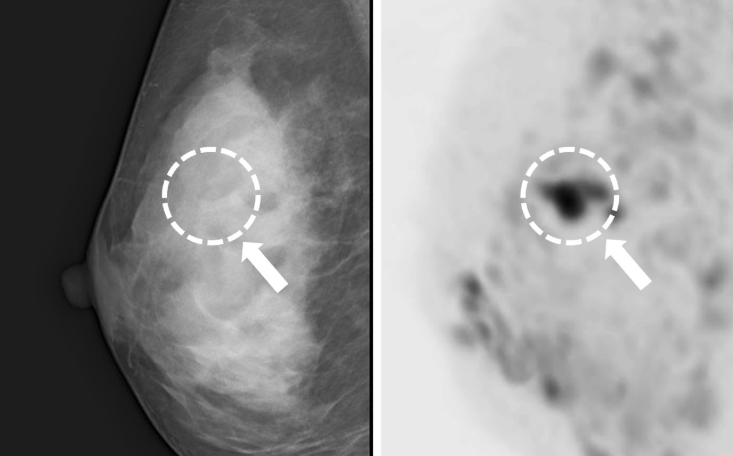

- 40세 이상 여성: 1~2년에 한 번씩 유방촬영(맘모그램) 권장